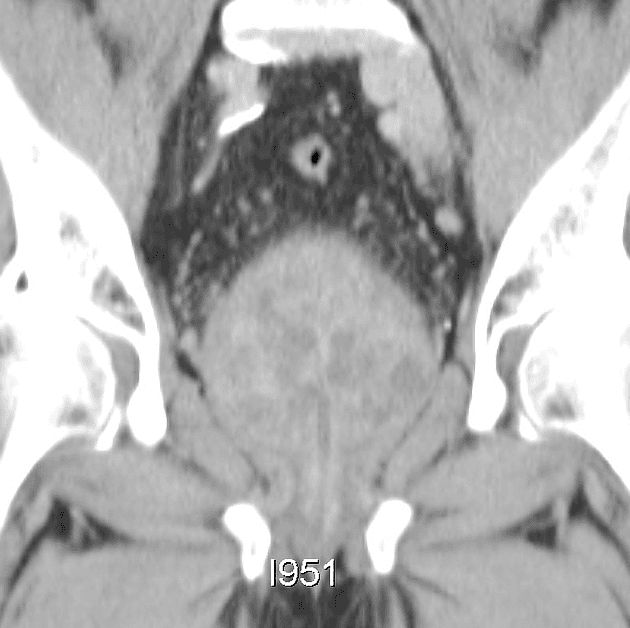

- Tuyến tiền liệt to, kích thước 52 x 56 x 57 mm (thể tích 87 ml).

- Tổn thương giảm tín hiệu T2 (T2 hypointense), giới hạn không rõ, dạng gai (spiculated), kích thước 7 x 5 mm, có hạn chế khuếch tán (restricted diffusion) và tăng quang sớm ở thì động mạch (early arterial enhancement), nằm ở vùng trung tâm/mũi tuyến, tại vùng ranh giới giữa PZpl/pm bên phải, gợi ý tổn thương PI-RADS 4 (suggestive of a PI-RADS 4 lesion).

- Các nốt tăng tín hiệu T2 (T2 hyperintense), giới hạn rõ (well-circumscribed), đặc trưng của tăng sản lành tính, kích thước tối đa 18 mm tại vùng TZ, phù hợp với nhóm PI-RADS 1 (consistent with PI-RADS 1 category).

- Thoát vị vào trong bàng quang (endovesical protrusion) tại vùng đáy tuyến.

Trường hợp này mô tả một tổn thương PI-RADS 4 ở vùng ngoại vi tại mức trung tâm/mũi tuyến, đặc trưng bởi hình dạng giảm tín hiệu trên T2, biên dạng gai, hạn chế khuếch tán trên DWI và tăng quang sớm ở thì động mạch – những dấu hiệu gợi ý mạnh đến ung thư tuyến tiền liệt có ý nghĩa lâm sàng. Mặc dù các bệnh lý lành tính như viêm tuyến tiền liệt mạn tính hoặc tổn thương teo hậu quả có thể bắt chước ung thư, nhưng sự kết hợp các hình ảnh này đòi hỏi phải sinh thiết định hướng để xác nhận bằng mô học. Ngược lại, các nốt ở vùng chuyển tiếp với đặc điểm tăng sản lành tính điển hình được phân loại là PI-RADS 1, phản ánh nguy cơ rất thấp. Đánh giá PI-RADS chính xác giúp định hướng quyết định lâm sàng, giảm thiểu sinh thiết không cần thiết đồng thời đảm bảo phát hiện các khối u ác tính.